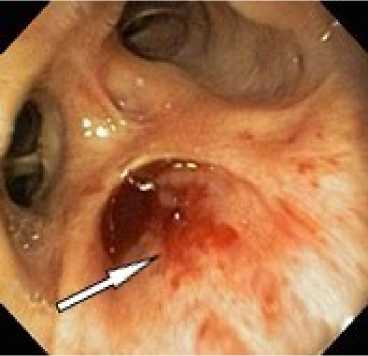

Эндоскопическая бронхоблокация основана на том, что после установки клапана в кровоточащей части лёгкого прекращается вентиляция воздухом, в соответствии с феноменом Эйлера Лильестранд-та происходит спазм сосудов лёгочной артерии в этой зоне, кровообращение лёгкого редуцируется и кровотечение останавливается (рис. 1). Механизм действия клапанной бронхоблокации состоит в формировании дренированного ателектаза.

А

Б

Рисунок 1. Эндо-фото. Признаки лёгочного кровотечения, после эндоскопического гемостаза посредством установки эндобронхиального клапана. А. Кровь в просвете бронха. Б. Просвет бронха с эндобронхиальным клапаном

Figure 1. Endoscopic photograph. Signs of pulmonary hemorrhage after endoscopic hemostasis via endobronchial valve placement. A. Blood in the bronchial lumen. Б. Bronchial lumen with endobronchial valve